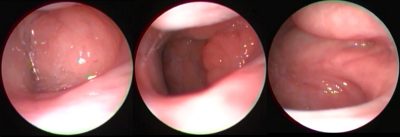

Geniz eti fazla derecede büyürse ya da gerilemezse ...

Geniz eti tüm insanlarda doğumdan itibaren bulunmaktadır. ...